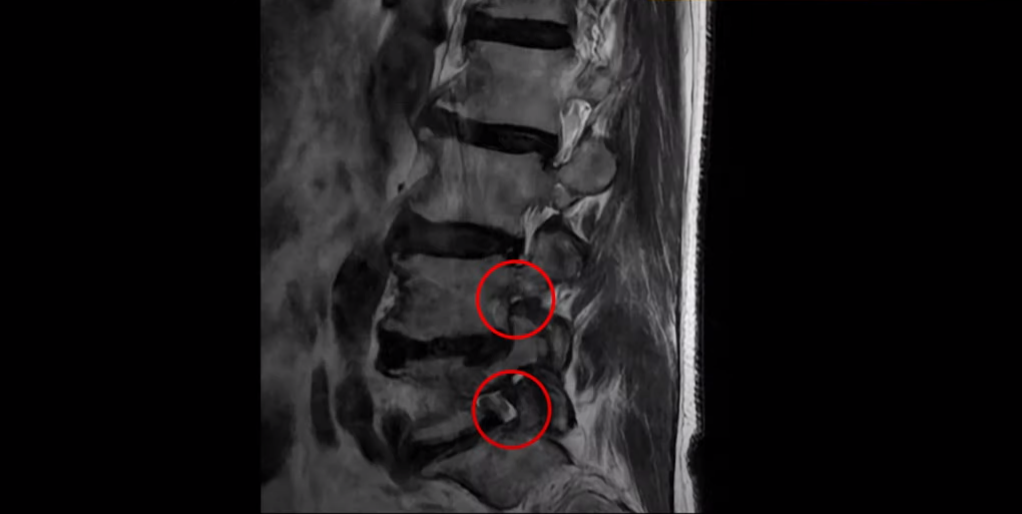

협착증은 노화 때문에 생기는 질환입니다. 나이가 들수록 노화와 퇴행 때문에 신경 구멍이 조금씩 좁아집니다. 이분도 신경 구멍이 좁아져 있습니다. 보시다시피 척추 여러 마디가 퇴행되어 있고

특히 왼쪽 신경가지가 빠져나가는 추간공들이 많이 좁아져 있습니다.

이분은 약 한달 전에 갑자기 왼쪽 다리를 아예 못 쓸 만큼 심하게 아프게 되었는데 허리를 펼 수도 없고 몇 미터 걸을 수도 없는 상태였습니다. 신경 주사를 여러 대 맞아도 전혀 듣지 않는 상태였는데 이분처럼 MRI 검사에서 신경구멍이 좁아져 있고 신경주사가 아예 듣지 않으면 십중팔구 수술하자는 얘기를 듣게 됩니다.

그런데 이분 신경구멍 좁아진 게 한 달 전에 갑자기 좁아졌을까요? 만일 1년 전에 전혀 안 아팠을 때 MRI를 찍었다면 최근에 아플 때 찍은 MRI와 많이 달라 보일까요? 정답은 거의 차이가 없다입니다. 아프기 전이나 아픈 후나 MRI로 보이는 신경 구멍의 크기가 같다면 그럼 왜 갑자기 한 달 전에 극심하게 아픈 증상이 생겼을까요? 그건 약해진 허리 주변 근육에 문제가 생겼기 때문입니다. 어떤 근육 문제가 이런 다리 방사통을 만들까요?